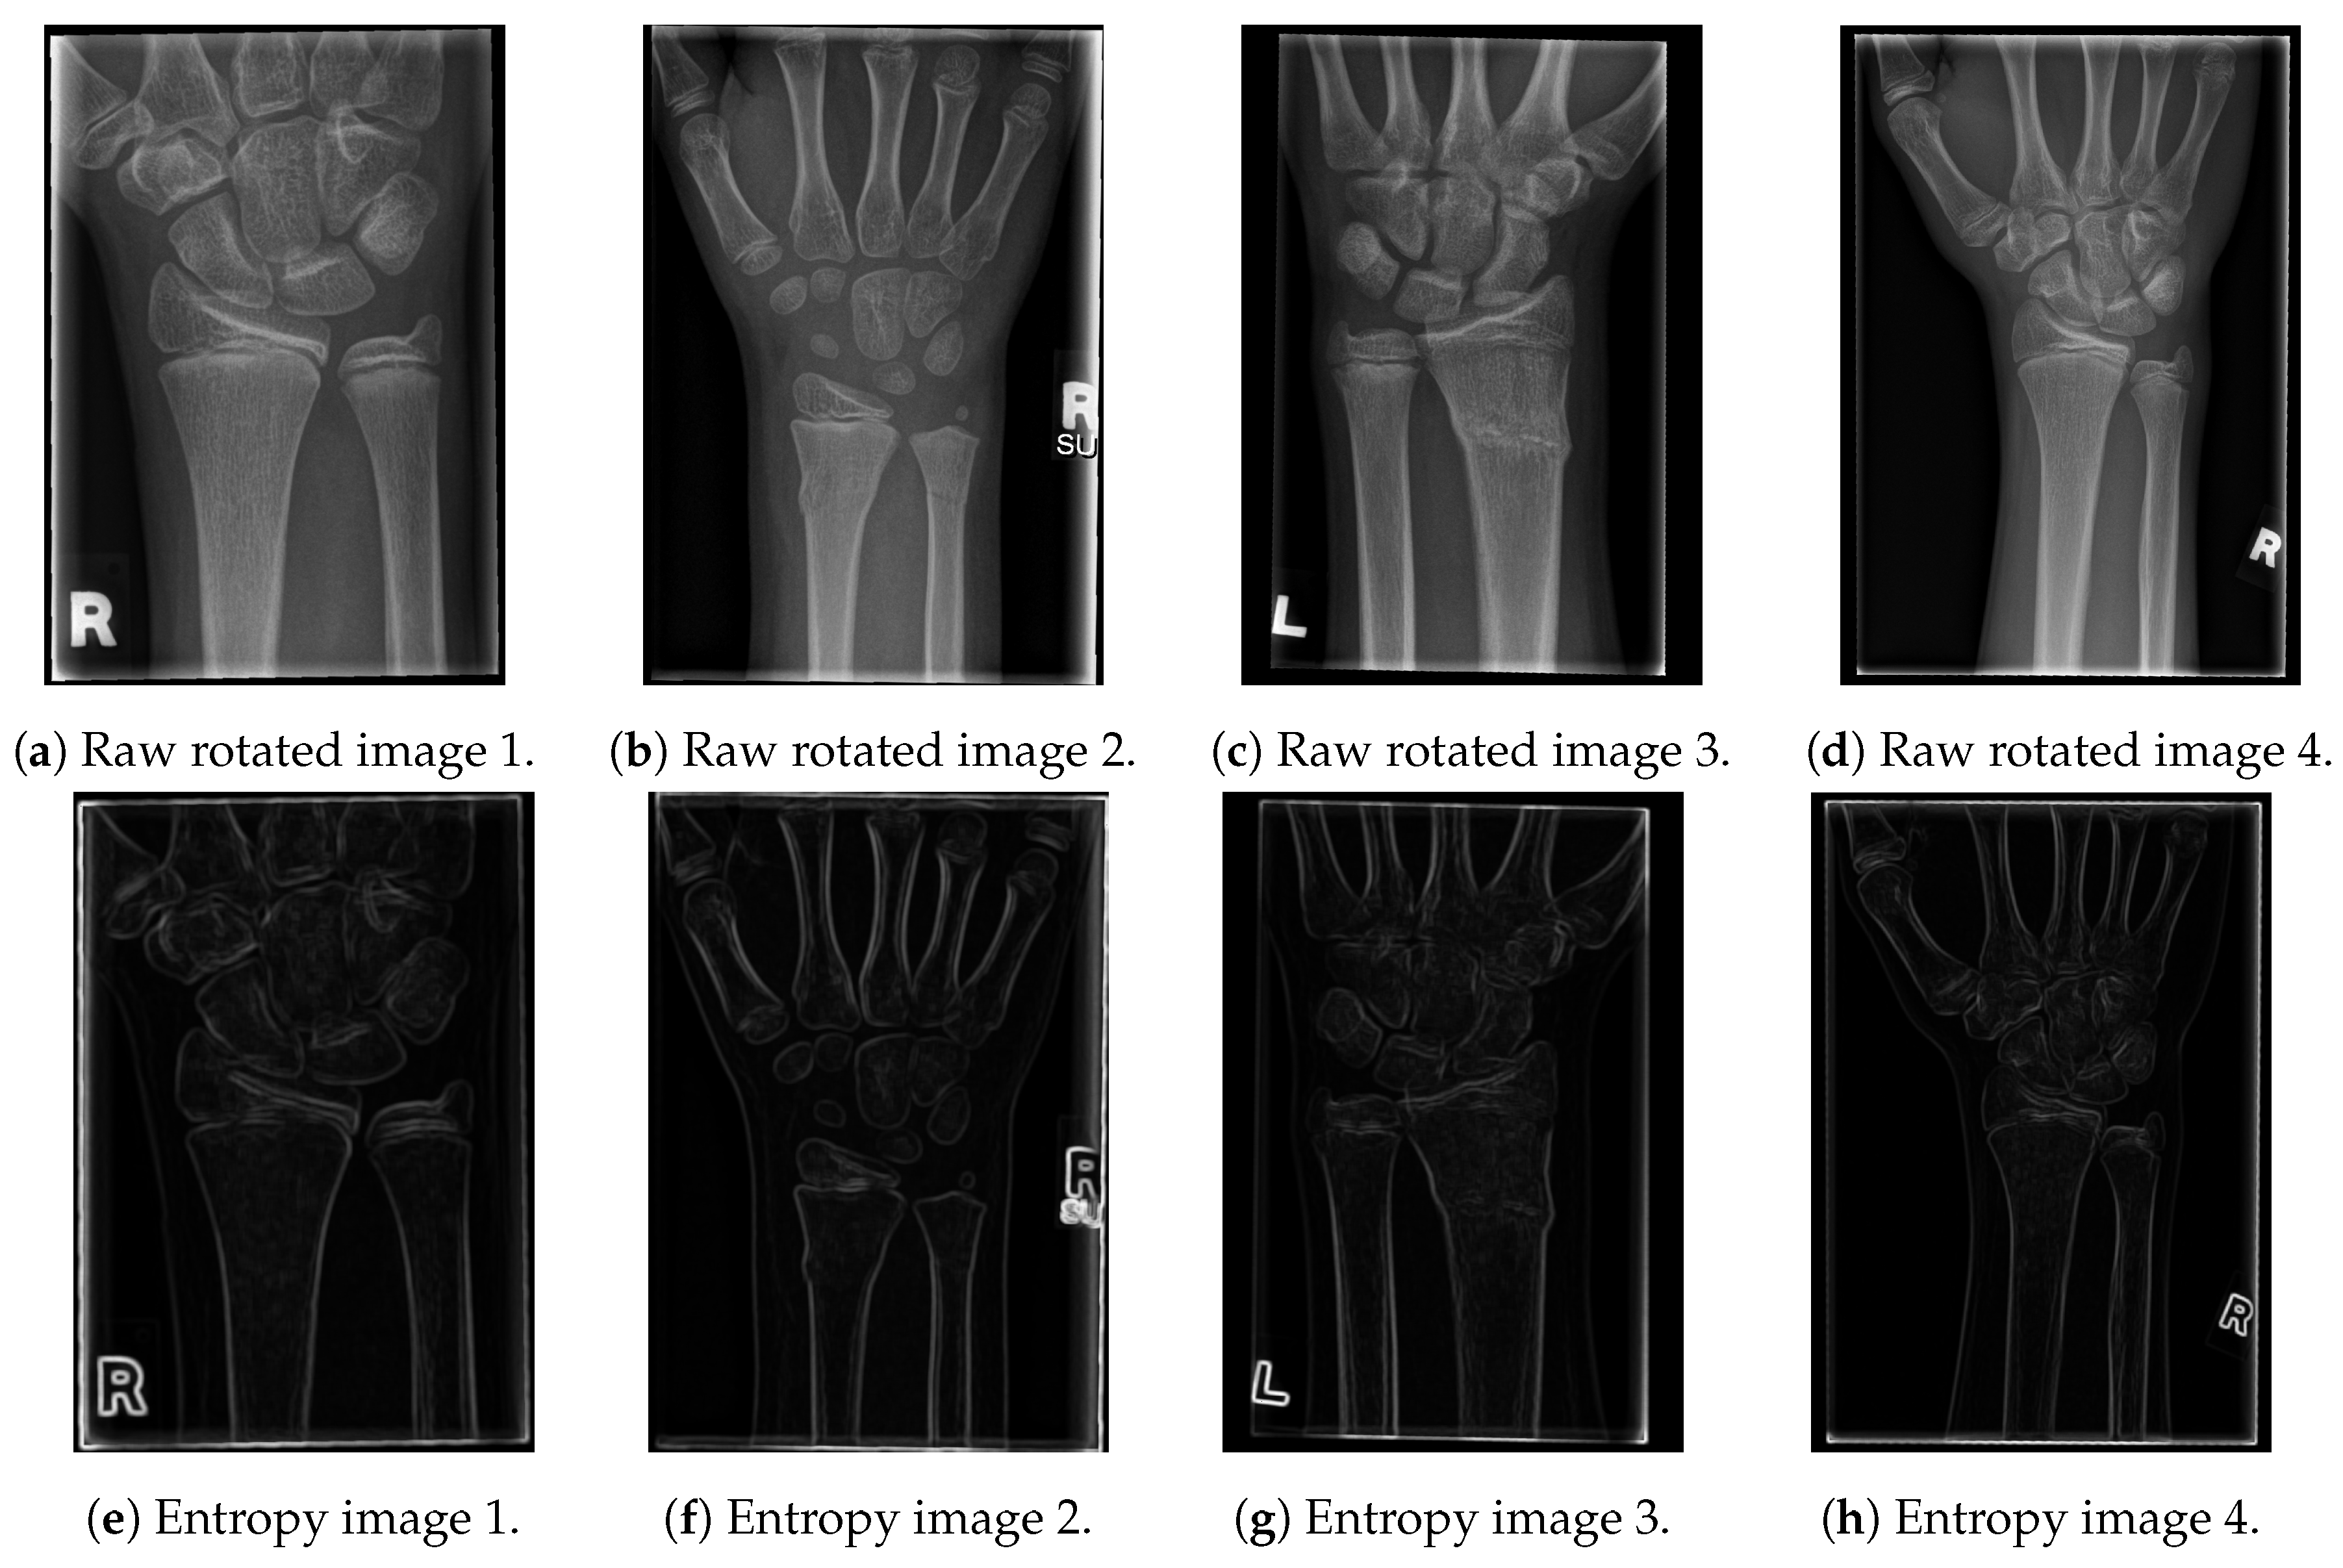

The resulting images are given in Figure 2.

Figure 2.

The results of the proposed entropy algorithm on X-ray images.

As shown in the entropy figures, the bone edges remain clearly visible, with only a small amount of tissue and noise left in their vicinity. In order to additionally emphasise the contours of the bones and to obtain a black and white image (with white pixels representing just bone contours), we have tested several edge-detection algorithms and proposed a new one, which outperformed all of them for the tested data-set [21,22]. In particular, the tested algorithms are: